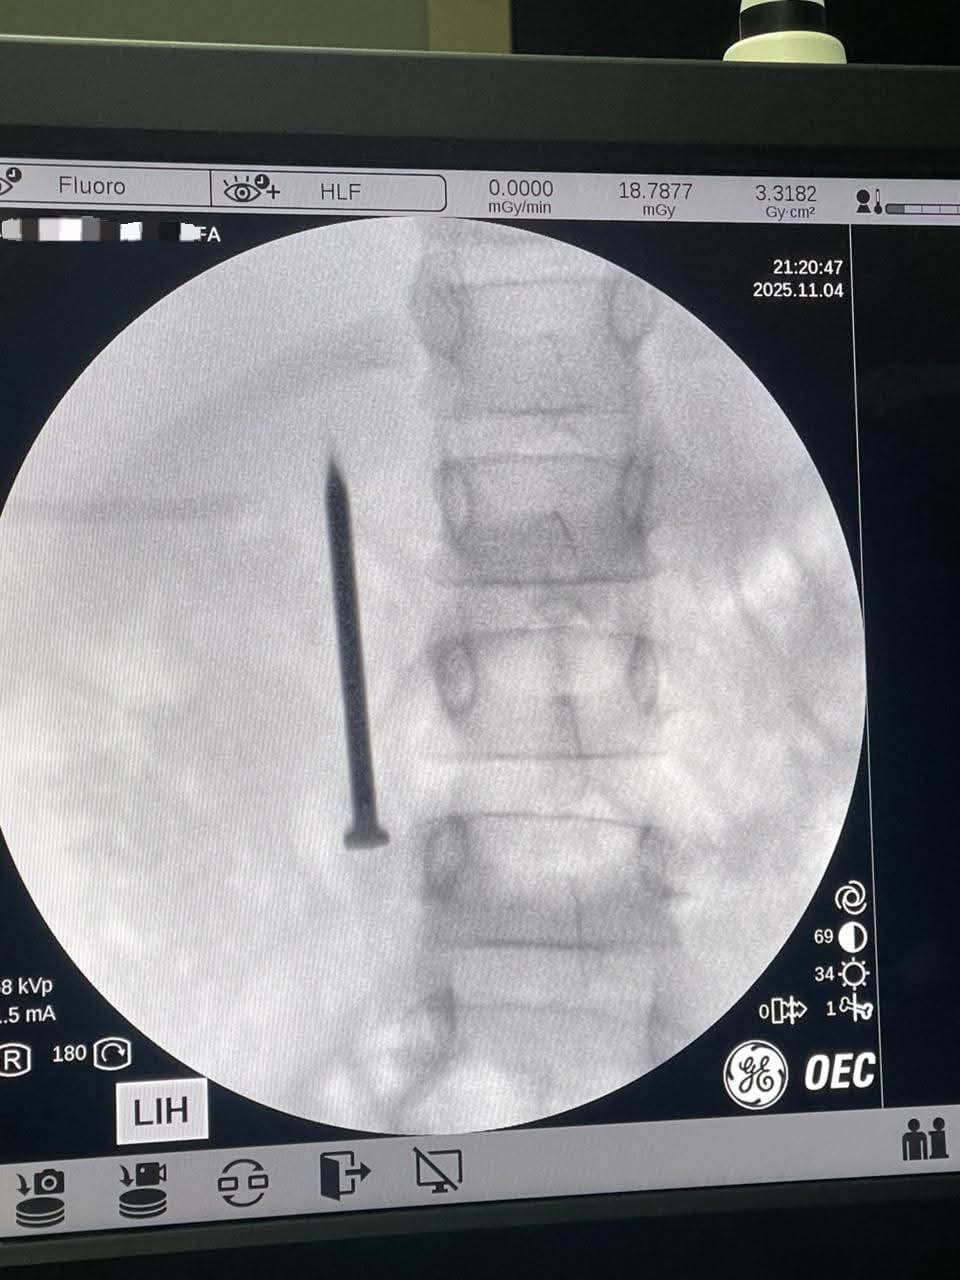

أعلن الدكتور أحمد القاصد، رئيس جامعة المنوفية، نجاح فريق طبي متخصص بوحدة مناظير الجهاز الهضمي بمعهد الكبد القومي في إنقاذ حياة طفلة تبلغ من العمر 7 سنوات، بعد ابتلاعها مسمارًا معدنيًا حادًا يبلغ طوله 4 سنتيمترات.

وأوضح رئيس جامعة المنوفية أن الفريق الطبي تمكن من استخراج المسمار الذي وصل إلى الجزء الأول من الأمعاء الدقيقة (الصائم) عبر إجراء منظار طارئ لم يستغرق سوى 20 دقيقة، متجنبًا بذلك خطر الثقب أو النزيف أو الانسداد المعوي الوشيك، حيث غادرت الطفلة المستشفى بصحة جيدة بعد التدخل الطبي السريع.

من جانبه، أكد الدكتور أحمد صيرة، أستاذ طب كبد الأطفال ورئيس وحدة مناظير الأطفال وقائد الفريق الطبي، أن استخدام المنظار كان الخيار الأمثل لتجنب إجراء عملية جراحية مفتوحة أكثر إرهاقًا للطفلة، مشددًا على أهمية التدخل السريع في مثل هذه الحالات لتفادي مضاعفات محتملة مثل الثقب أو النزيف أو الانسداد المعوي.